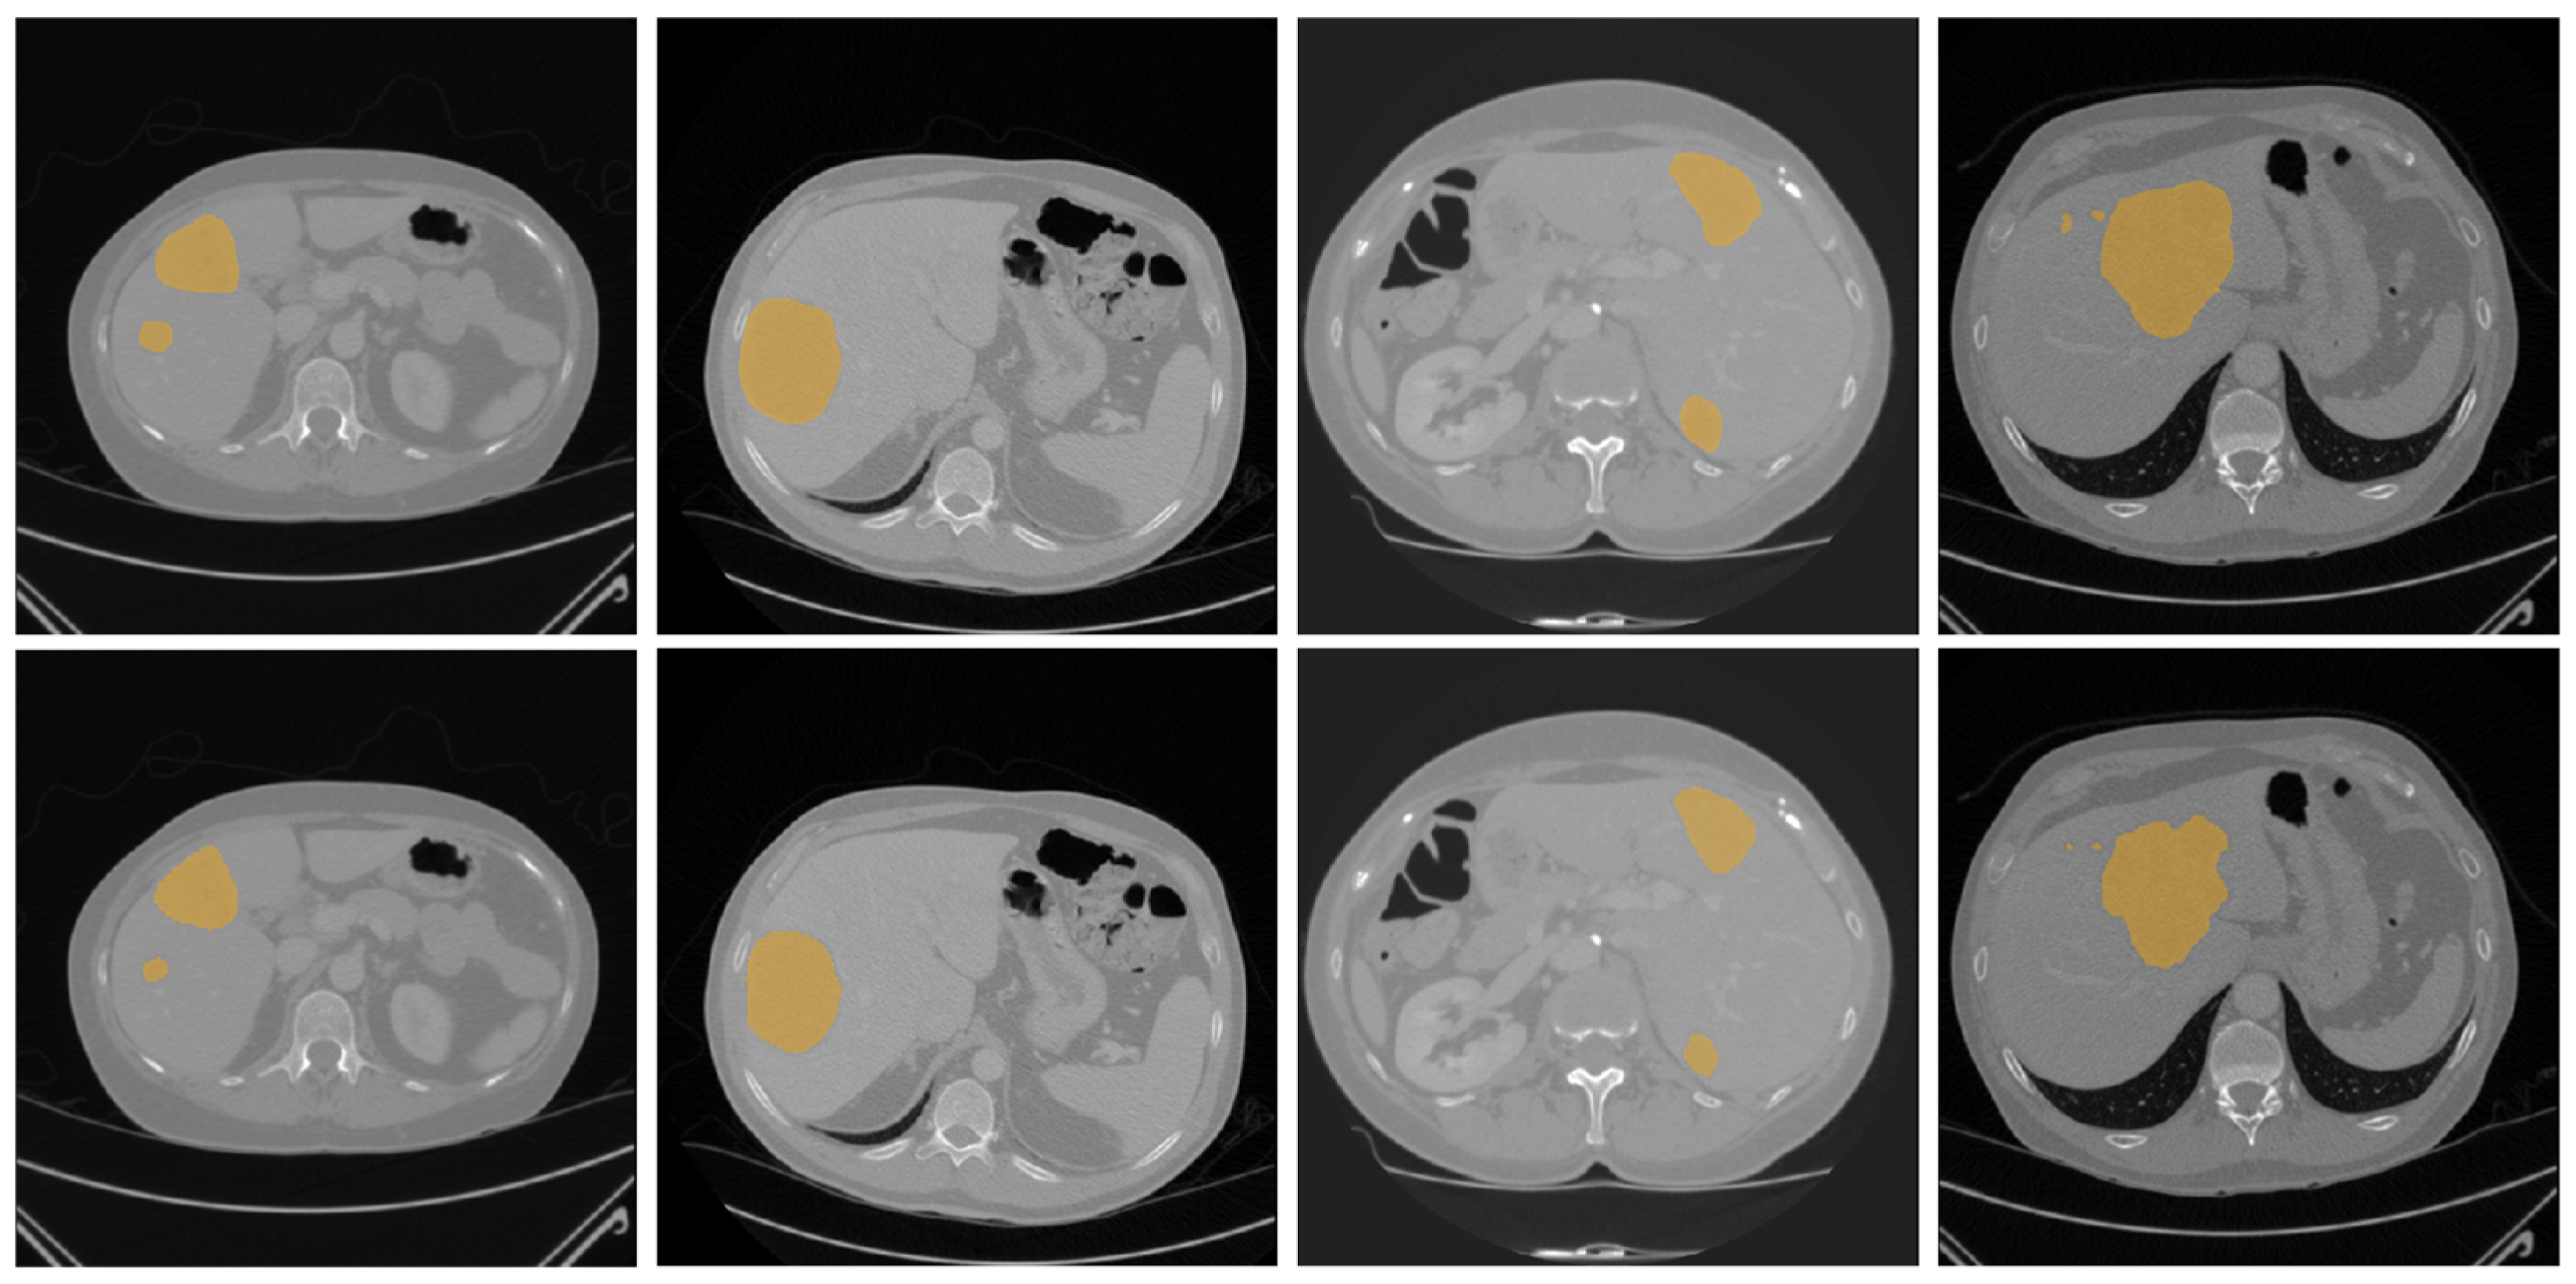

Figure 4 and Figure 5 illustrate some examples of the liver tumor segmentation results with our model from the LiTS dataset and the 3DIRCADb dataset, respectively. Visual inspection of the segmentation results reveals that the predicted tumor regions are properly aligned with the ground truth in terms of both the number of tumors and their morphology.

Figure 4. Examples of tumor segmentation results of the proposed model over the LiTS dataset. Upper: the ground truth; bottom: the predicted tumor regions.